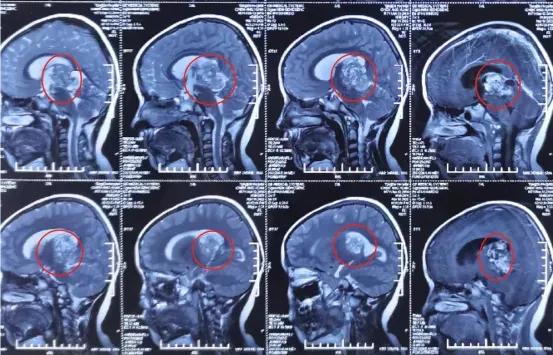

术前影像学资料: